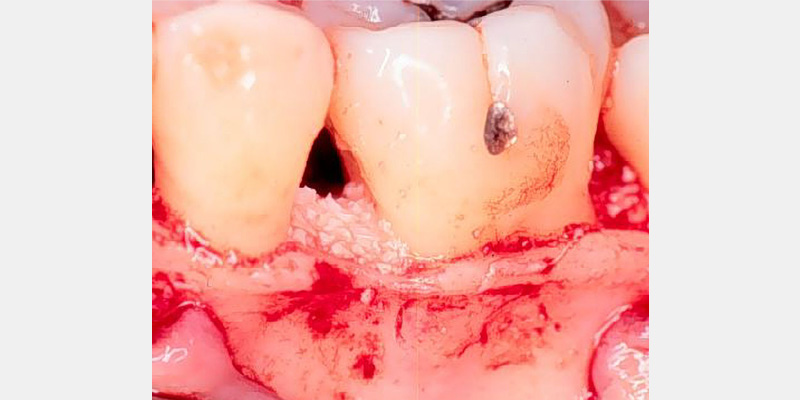

The primary goal of periodontal treatment is the maintenance of health, function and esthetics of the natural dentition and supporting structures. When necessary, this includes tooth and tissue replacement with regeneration and dental implants (Figs. 3A, 3B).

Periodontal regeneration includes the recreating of periodontal ligament, cementum and alveolar bone along the previously diseased and denuded root surface. The evidence supporting guided tissue regeneration is vast and growing. For decades dental surgeons have been using, with high levels of predictability, resorbable and non-resorbable barrier membranes in passive tissue engineering around teeth and dental implant dehiscence and fenestrations.3, 4 By employing active tissue engineering, new levels of predictability and success can be reached to resolve hard and soft tissue, periodontal and other orofacial defects.

Periodontal defects include the intrabony and furcation-type defects, as well as with gingival recession or loss of attachment. The periodontal literature validates the regenerative potential of biologically active bone replacement grafts (Figs. 1–5).5, 6, 7 Periodontal regeneration with histological evidence of new cementum, periodontal ligament and alveolar bone has been shown in the human model with a recombinant growth factor and a porcine (pig)-derived protein.8, 9, 10